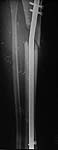

Briefly 22 yo male rollover MVA 1 yr ago. Isolated lower extremity injury. 3b open distal 1/3 femur and proximal 1/3 tib/fib (ipsilateral). Lots of debris dirt grass clothes and carpet. Treated emergently with debridement and spanning frame.

Flaped within week. Frame removed and converted to nails (retro femur) prior to flap. Had proximal tibial defect after initial debridement. Soft tissue envelope healed.

S/P Nailing

AP

lateral